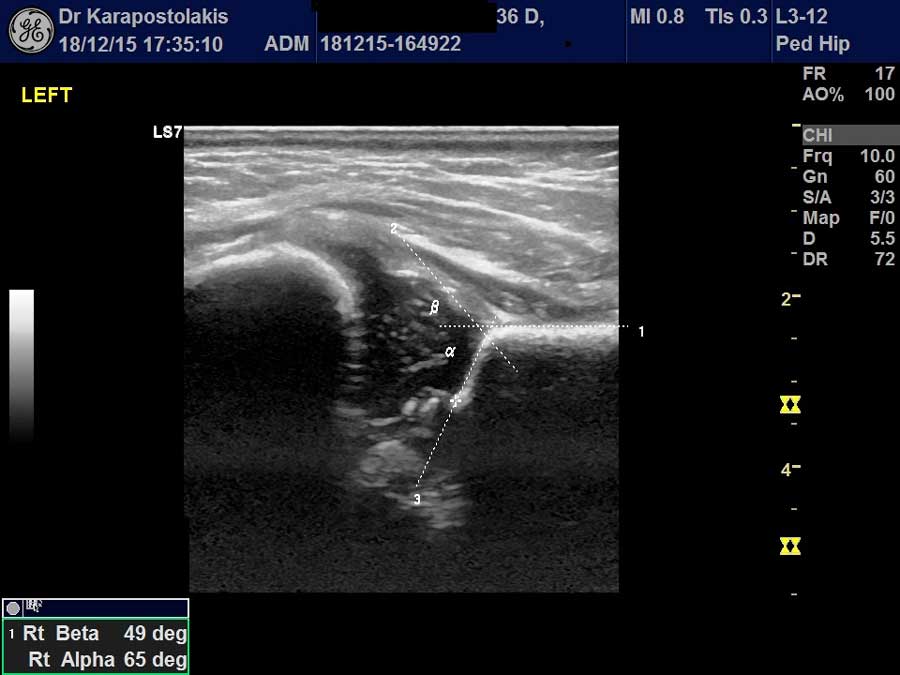

Στα παιδιά διενεργούνται οι κάτωθι υπερηχογραφικές εξετάσεις

- Υπερηχογράφημα θυρεοειδούς αδένα και παραθυρεοειδών αδένων